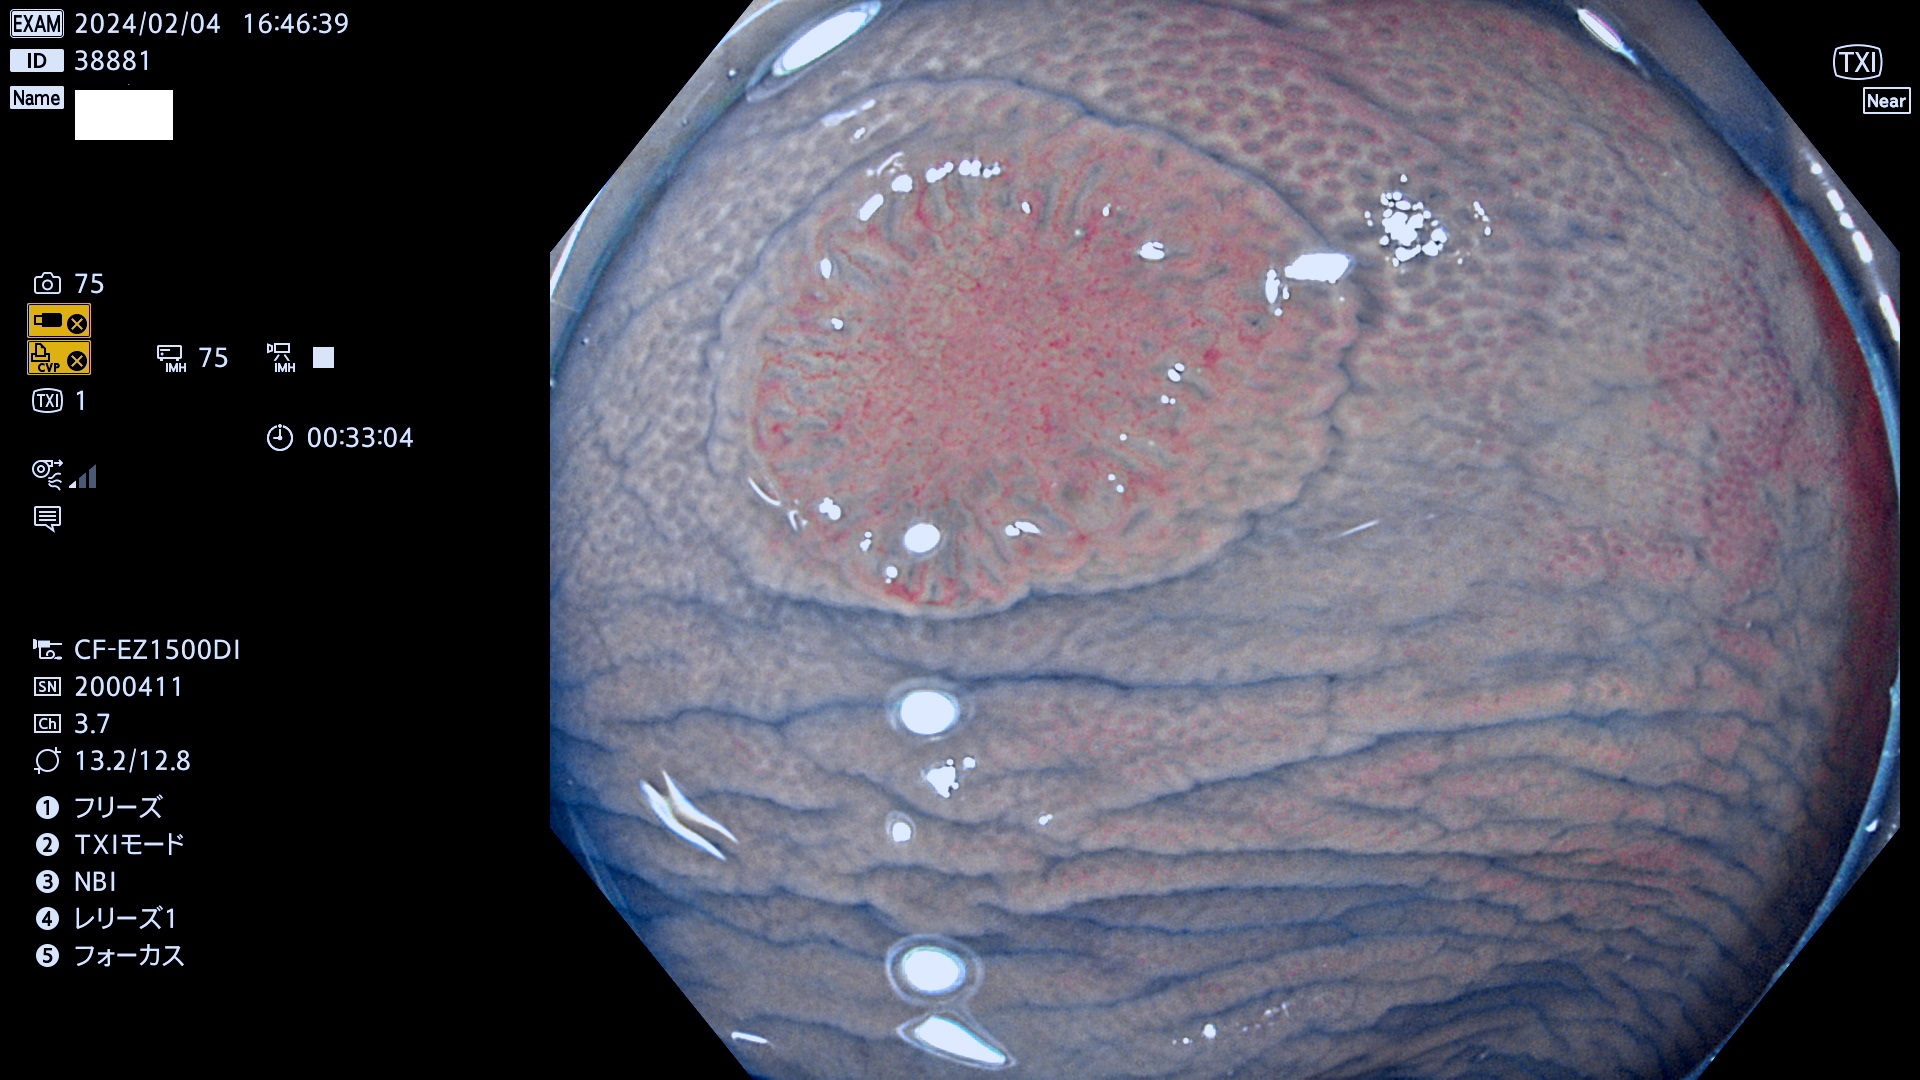

表面型腺腫(Flat Adenoma)の中で、完全に平坦な物をUb、陥凹している物をUcと呼びます。平坦隆起型(Ua)よりも、発見が難しく危険な病変です。

毎週の検査(木・金・土・日)に発見されたUb、Uc型・腺腫を、その週の日曜の夜にUPし1週間、提示します。

抽出の対象期間 2024年2月1日(木)〜2月4(日)の4日間(40件の検査)12件